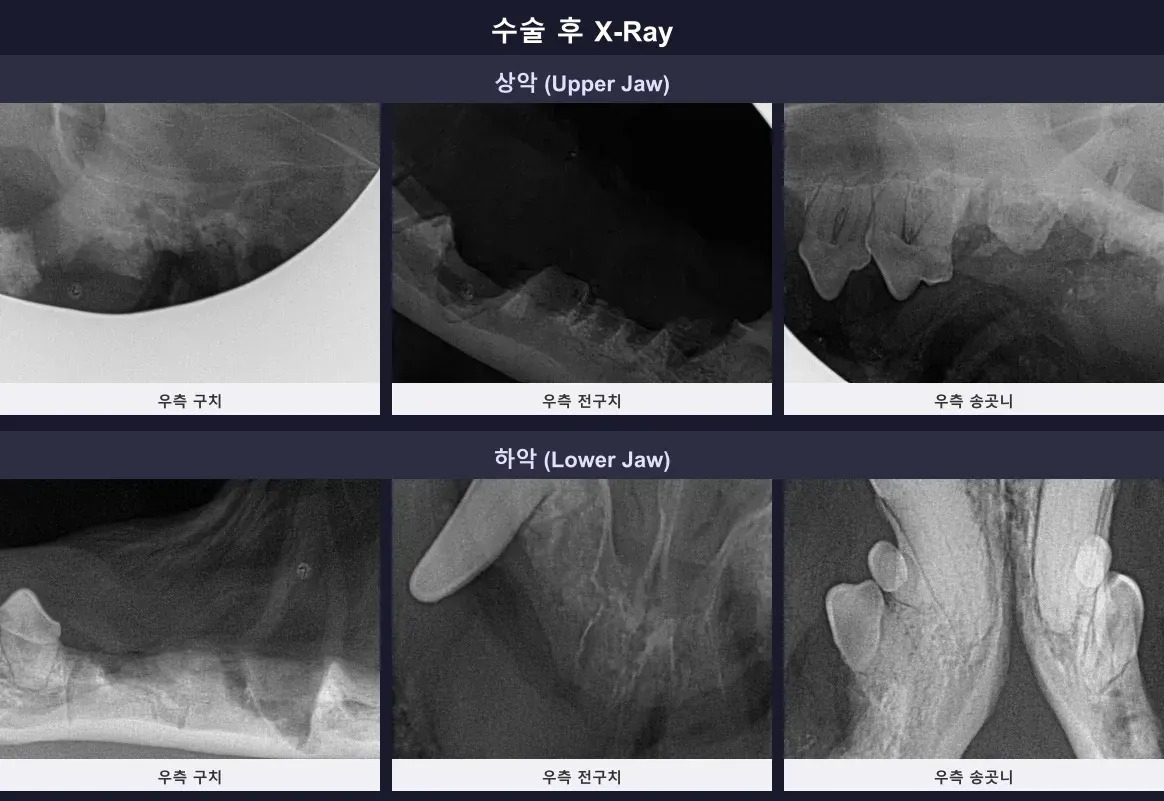

수술 후 구강 방사선을 다시 촬영하여 남은 뿌리 없이 완벽하게 광주 발치 수술이 완료되었음을 확인했습니다. 27개라는 많은 치아를 잃었지만, 통증과 염증의 원인이 제거되었기 때문에 두부의 전반적인 건강 상태는 훨씬 좋아질 것입니다.

수술 후 남은 잔존 뿌리 없이 깔끔하게 완료된 구강 X-ray 결과